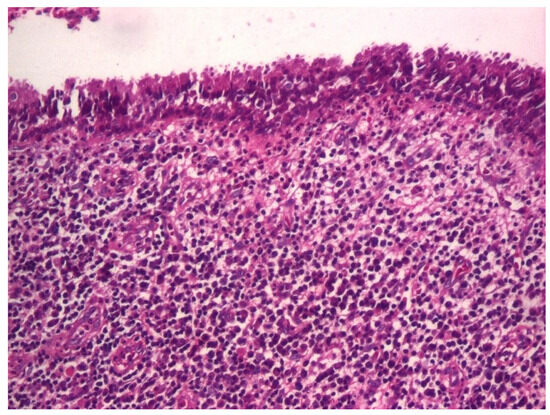

3.1.3. Analysis of Histopathologic and Immunohistochemical Results

| Histopathologic Aspects | Number of Patients |

|---|---|

| Cholesteatom | 276 |

| Polip | 180 |

| Tympanic membrane mucosa chamber, epithelium with apocrine-like cells, and chronic inflammatory infiltrate | 128 |

| Cell Types | Percentage |

| Lymphocytes T | 42.55% |

| Lymphocytes B | 31.45% |

| Macrophages | 26.00% |